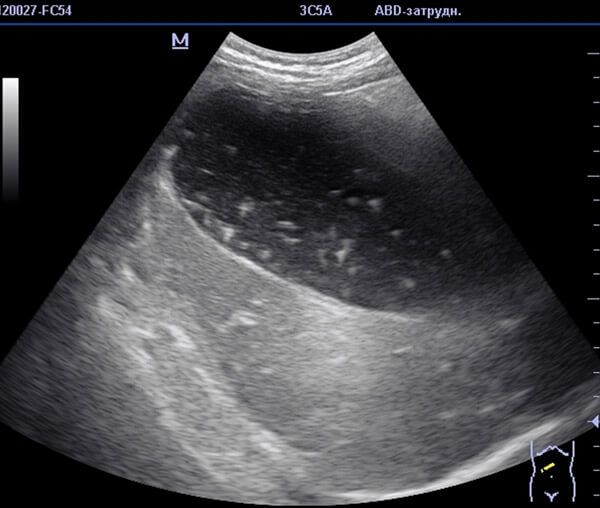

Благодаря инструментальным методам диагностики получается визуальная картина печени, желчного пузыря, протоков и желудка. В результате инструментальной диагностики врач может обнаружить закупорку протоков, оценить степень поражения внутренних органов, задействованных в транспортировке желчи.

В качестве инструментальной диагностики применяются:

- УЗИ;

- эндоскопическая ретроградная холангиопанкретография;

- МРТ;

- чрезкожная чрезпеченочная холангиография.